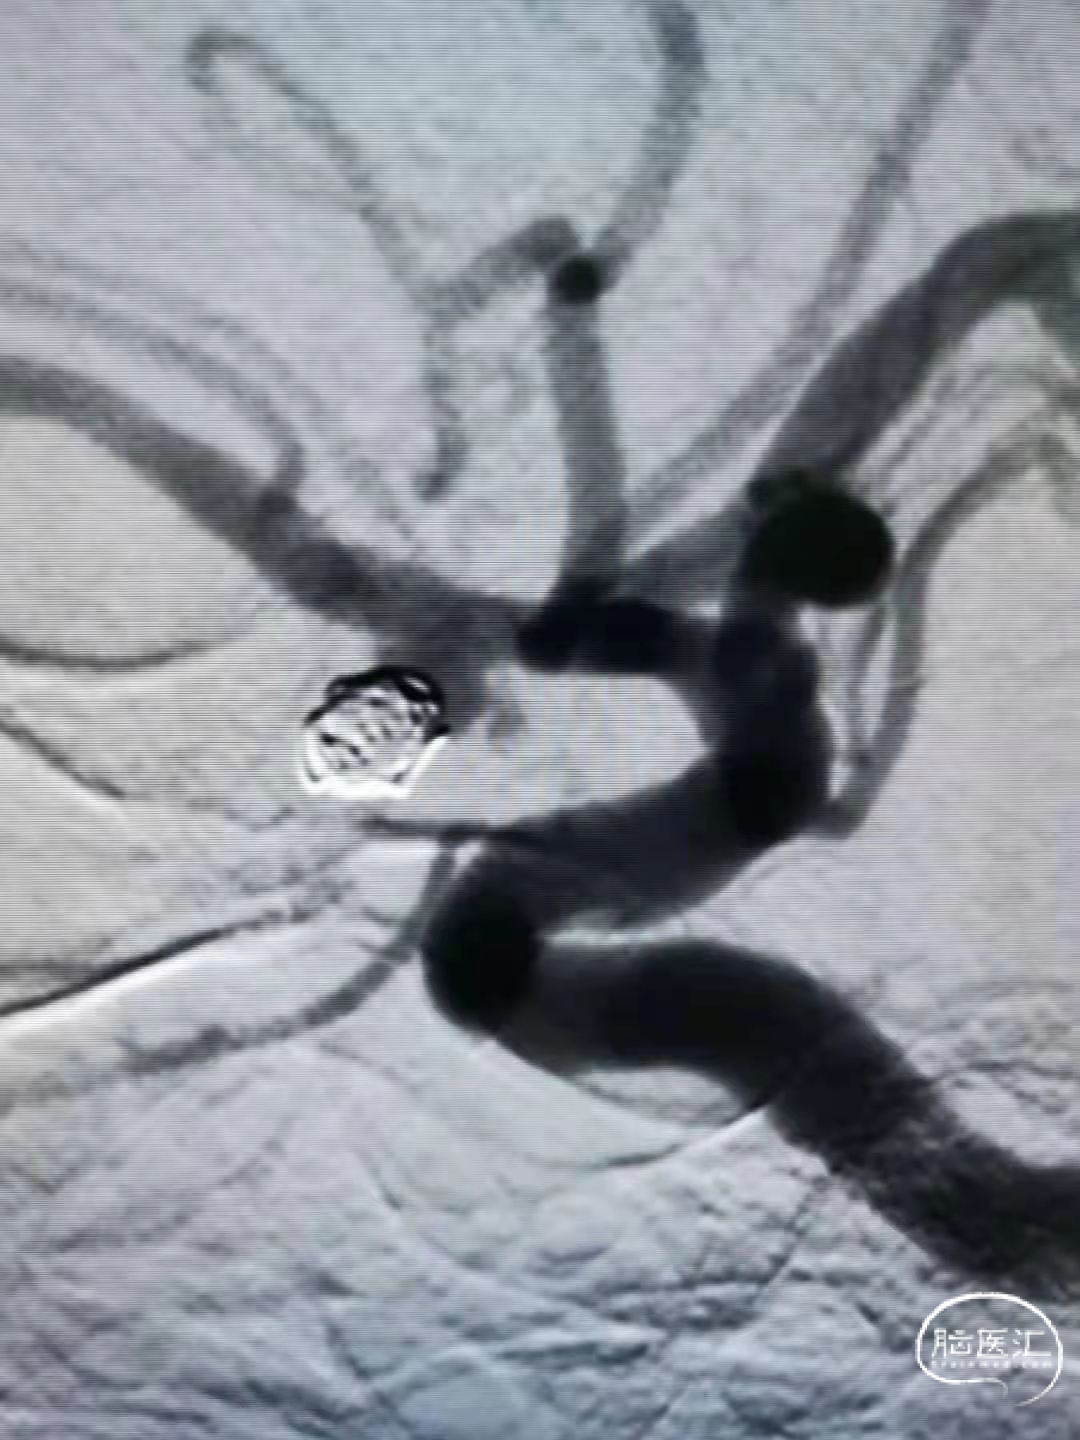

大脑后动脉P2段宽颈动脉瘤。瘤体6.18×7.35mm,瘤颈约7mm,近、远端载瘤血管直径2.25mm,1.77mm。

小径支架微导管通过性更佳(如下视频)。

后释放稳定,打开良好(如下视频)。

后释放稳定,可见弹簧圈压缩及瘤内通道建立(如下视频)。

术后造影,动脉瘤致密栓塞,载瘤动脉保存完好(如下视频)。